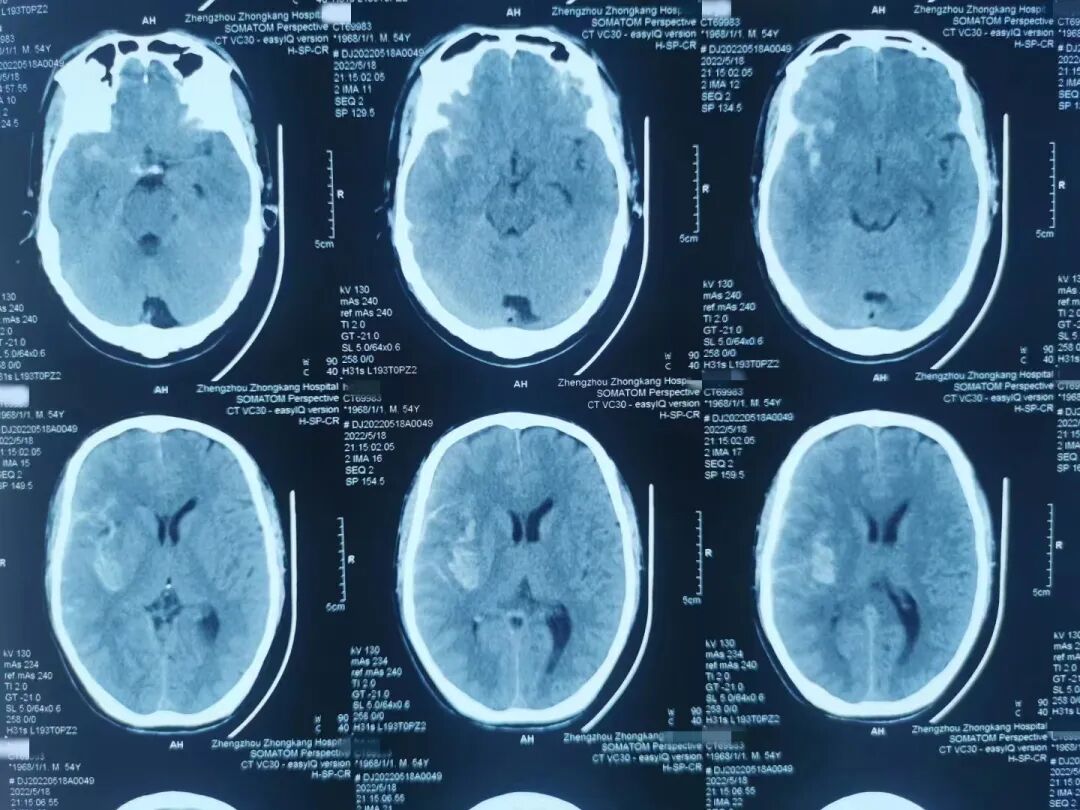

因何某家属均在外地,暂无法入密,家属决定先保守观察。5月18日晚,54岁的何某突然意识加深,复查头颅CT显示

“ 动脉瘤破裂 ”

图片

需要紧急进行“弹簧圈栓塞术

医院了解情况后,立即通过视频连线的方式和患者妻儿沟通病情,经家属同意手术后,迅速开展手术,与“死神”抢时间,经全力救治,确保了患者手术的成功。